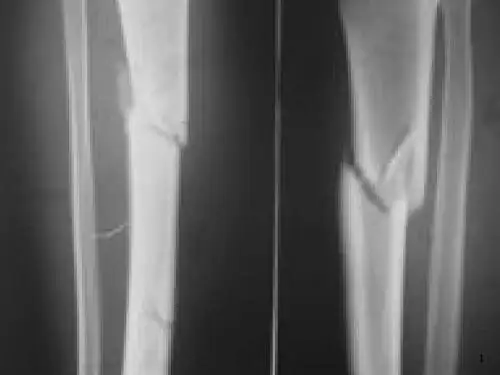

骨折愈合过程中,膜内化骨与软骨内化骨在其相邻处互相 交叉,但前者远比后者为快,故应防止在骨折处形成较大的血 肿,以减少软骨内化骨的范围,加速骨折愈合。而且骨性骨痂 主要是经膜内化骨形成,并以骨外膜为主。因此,骨外膜在骨 痂形成中具有重要作用,任何对骨外膜的损伤均对骨折愈合 不利。骨内膜和骨外膜的成骨细胞增生在骨折端内、外形成 的骨样组织逐渐骨化,形成新骨,称为膜内化骨。随新骨的不 断增多,紧贴骨皮质内、外面逐渐向骨折端生长,彼此会合形 成梭形,称为内骨痂和外骨痂〔图61-19(1)〕。骨折断端间及 髓腔内的纤维组织亦逐渐转化为软骨组织,并随软骨细胞的增 生、钙化而骨化,称为软骨内化骨,而在骨折处形成环状骨痂 和髓腔内骨痂.两部分骨痂会合后,这些原始骨痂不断钙化而 逐渐加强,当其达到足以抵抗肌收缩及成角、剪和旋转力时, 则骨折已达到临床愈合,一般约需4~8周。此时X线片上可见 骨折处四周有梭形骨痂阴影,但骨折线仍隐约可见。